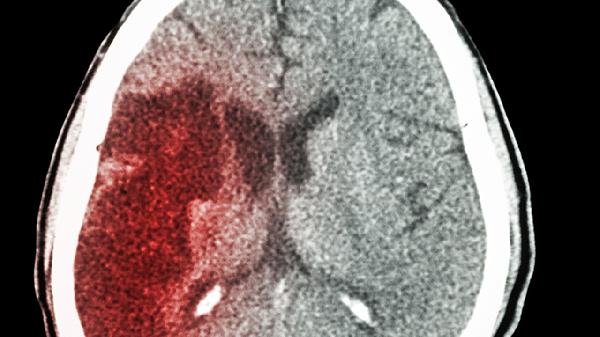

出血量是决定预后的核心指标。少量出血<30ml通常对周围脑组织压迫较轻,通过药物降颅压和血压管理,神经功能缺损多可逆;大量出血>50ml易引发脑疝,需紧急手术清除血肿,术后常遗留运动或语言障碍。临床常用CT评估血肿体积变化。

基底节区作为运动传导通路关键节点,出血易导致对侧肢体偏瘫。若内囊后肢受累,上肢屈曲和下肢伸直痉挛更显著;若累及语言中枢优势半球,可能伴随失语。早期弥散张量成像可评估锥体束损伤范围。